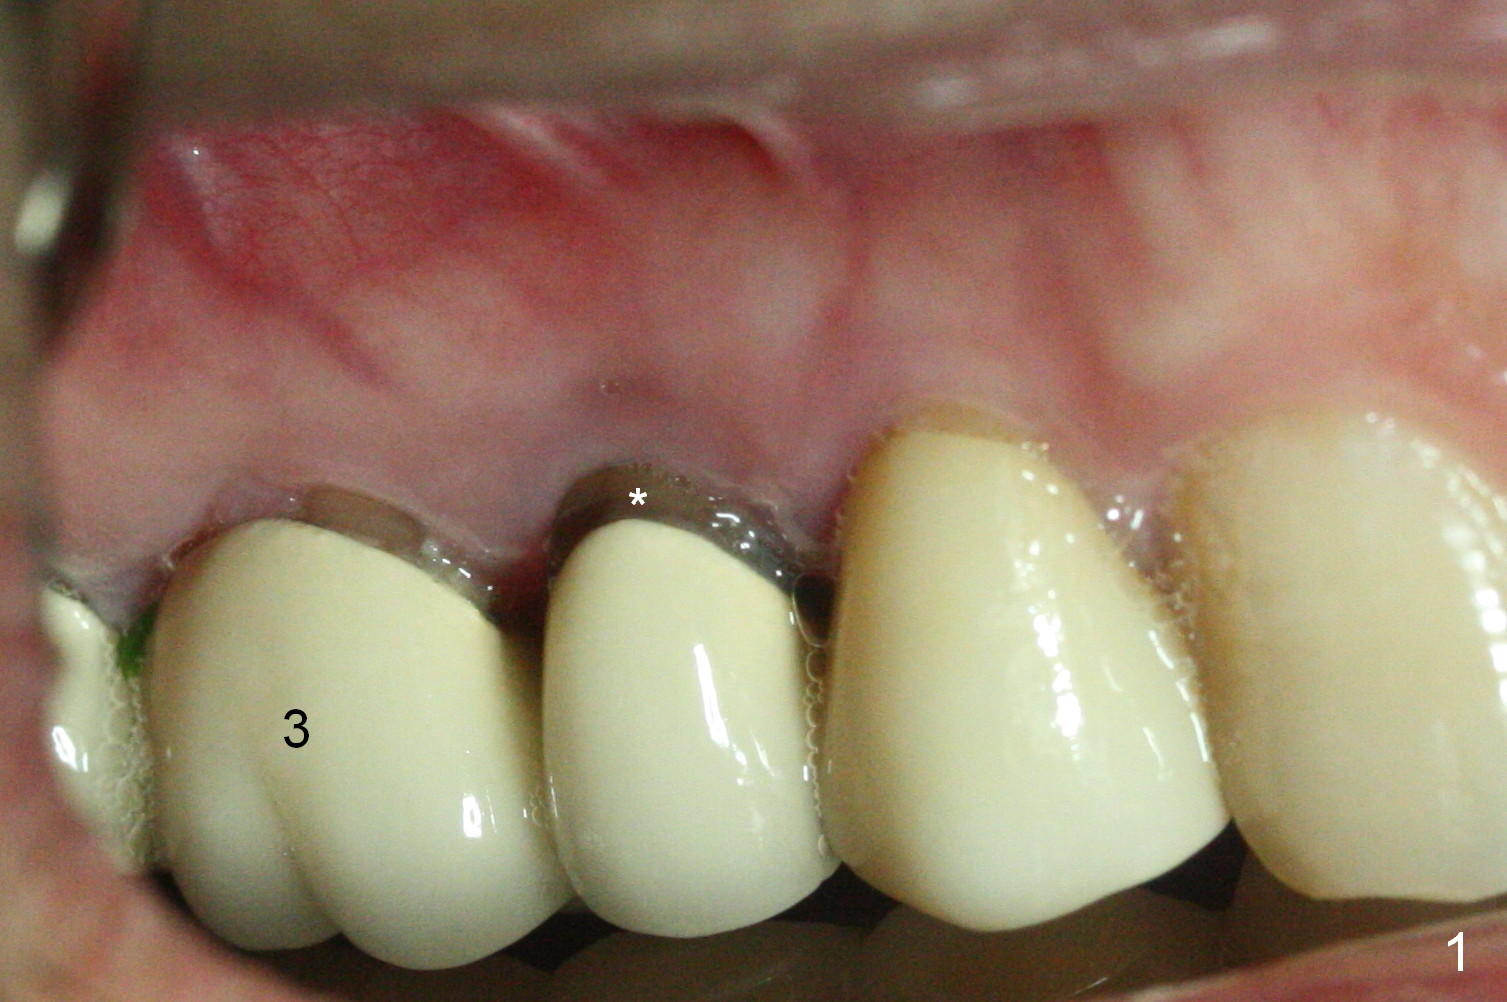

A 42-year-old man returns with chief complaint of chipped tooth at #3. Crowns at #3 and 4 are splinted (Fig.1). The tooth #4 is discolored (^). X-ray exam shows post (P) -induced Root (R) split with severe bone loss at #4 (Fig.2). To decrease periimplantitis, use an implant as narrow as possible (4 mm) and as long as apical bone allows (13 mm, IBS, Fig.3). Section the retainer at #3 and remove the tooth #4 (Metronidazole). Prepare PVS impression to record socket morphology. Magic Expanders are to be applied for osteotomy and sinus lift if possible. Finally fabricate splinted provisional at #3 and 4.